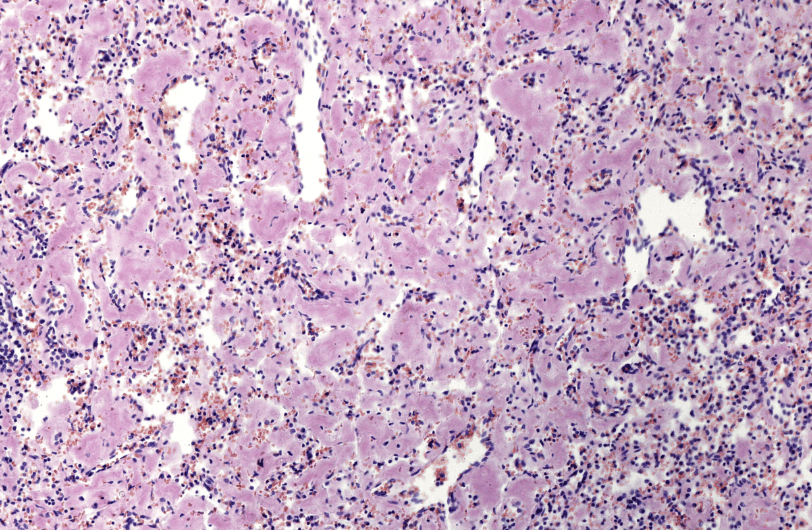

L’amiloidosi è una patologia che si caratterizza per l’accumulo di aggregati proteici (amiloidi) che si depositano nei tessuti danneggiando gli organi.

Le forme più comuni della malattia sono l’amiloidosi AA ed è legata a un’infiammazione cronica e l’amiloidosi AL in cui i depositi derivano da frammenti di immunoglobine.